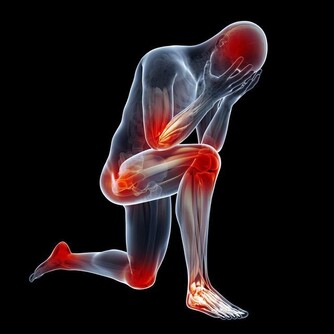

除此之外,老人缺乏蛋白質,身體也會體現以下3個症狀:

首先,老人缺乏蛋白質會對情緒造成影響,從而導致頭昏腦脹、情緒低落的情況出現。這是因為多巴胺和5-羥色胺等神經遞質需要蛋白質進行組合,而蛋白質的缺失,自然也會對神經遞質造成一定影響。

其次,老人缺乏蛋白質也會較為容易出現脫髮的情況。角質蛋白是構成頭髮其中的一種物質,也屬於蛋白質的一種。而缺乏蛋白質會對頭髮的堅固性造成影響,從而引起脫髮。

最後,人體的免疫細胞由也是由蛋白質組成,一旦身體缺乏蛋白質就會使得免疫系統功能變差,從而使得免疫力下降。因此,老人缺乏免疫力也會對體質造成影響。